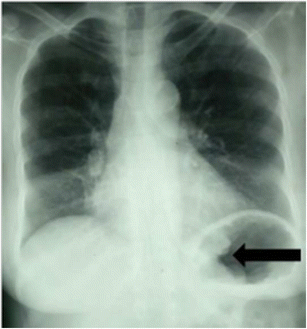

Epidemiology gastric diverticula are rare and c. Weight loss surgery is about reducing your weight and gaining good health. Gastric diverticula are sac like projections that usually originate from the gastric fundus most commonly on the posterior surface. They are the least common of the gastrointestinal diverticula.

Cain jc jordan gl jr comfort mw gray hk. J am med assoc. The gas tric fundus is dened as the portion of the stomach craniad to the gastric car dia. Commonly accompanying this are abnormally dilated short gastric veins which pass from the splenic vein to encircle the gastric fundus and form gastric fundal varices.